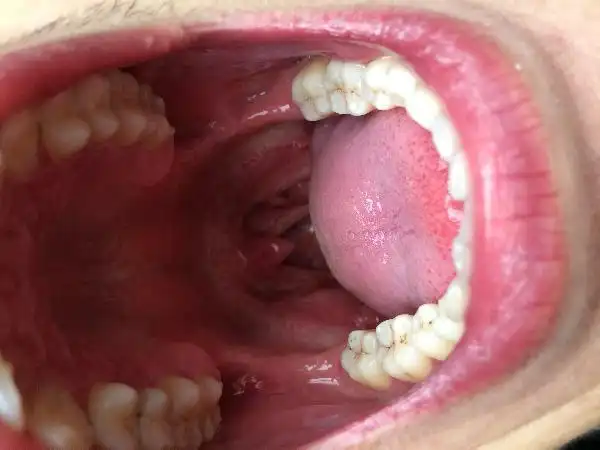

一例男性hpv口腔感染病例治疗费用高,就医情况严峻口腔疾病得不到有效

这是口腔尖锐湿疣吗,请专业的帮我看一下

健康美好生活计划# 你好医生,我怀疑口腔感染hpv?

口腔感染hpv舌头图片